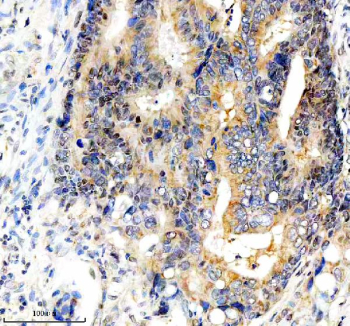

Immunohistochemical staining of FBXO7 using anti-FBXO7 antibody. FBXO7 was detected in a paraffin-embedded section of human colon cancer tissue. Heat mediated antigen retrieval was performed in EDTA buffer (pH 8.0, epitope retrieval solution). The tissue section was blocked with 10% goat serum. The tissue section was then incubated with 2 ug/ml rabbit anti-FBXO7 antibody overnight at 4oC. Peroxidase Conjugated Goat Anti-rabbit IgG was used as secondary antibody and incubated for 30 minutes at 37oC. The tissue section was developed using an HRP secondary and DAB substrate.